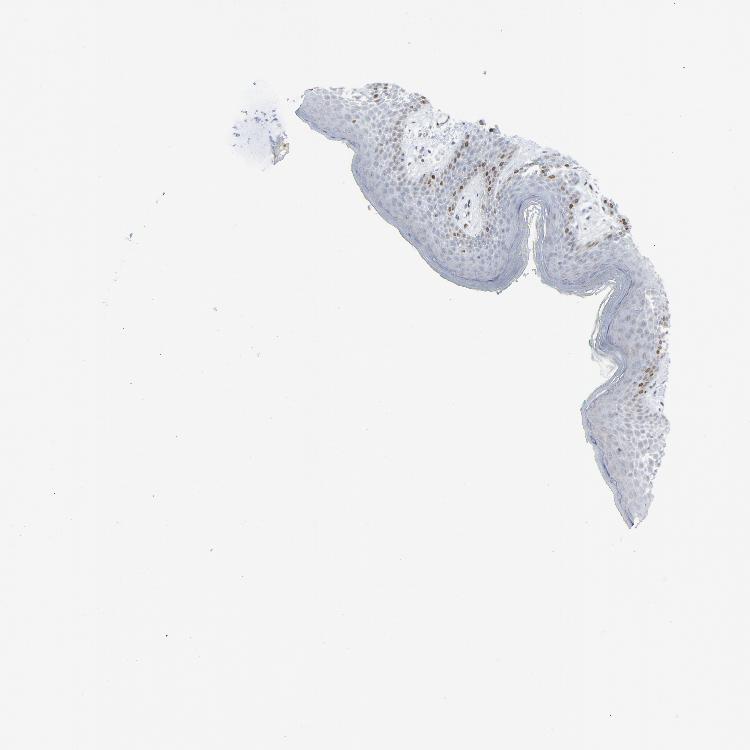

SKIN 2 - Antibody stainingi

Antibody staining in the annotated cell types in the current human tissue is reported as not detected, low, medium, or high, based on conventional immunohistochemistry profiling in selected tissues. This score is based on the combination of the staining intensity and fraction of stained cells.

Each image is clickable and will lead to virtual microscopy that enables deeper exploration of all samples and also displays staining intensity scores, fraction scores and subcellular localization as well as patient and tissue information for each sample.

Antibody HPA002317

Cells in basal layer Medium

Cells in corneal layer Not detected

Cells in granular layer Not detected

Cells in spinous layer Low

Endothelial cells Not detected

Extracellular matrix Not detected

Fibrohistiocytic cells Low

Langerhans cells Not detected

Lymphocytes Low

Melanocytes Not detected

Vascular mural cells Not detected